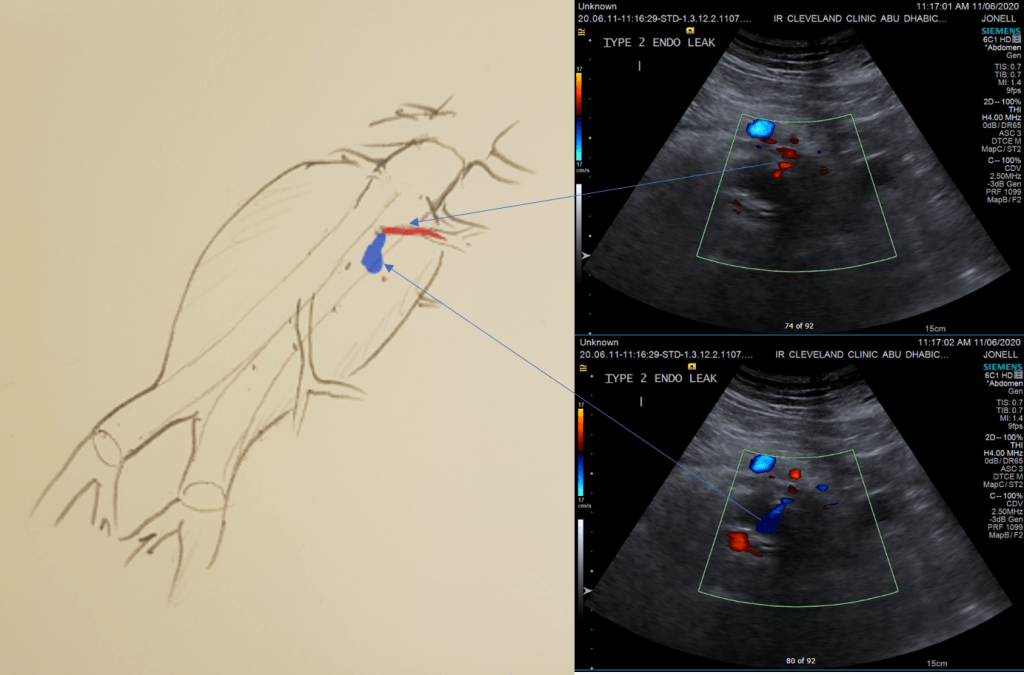

While CT failed to locate this endoleak, abdominal duplex ultrasound did showing flow from a small surface vessel (duplex below, figure at beginning of post). It was not the inferior mesenteric artery which can be treated endovascularly (link) or laparoscopically (link). CT scan suggested that it was one of those anterior branch vessels that one would encounter in exposing the aorta. Usually these were higher up as accessory phrenic arteries, but these fragile vessels, larger than vasovasorum, but smaller than named aortic branches, are seen feeding the tissues of the retroperitoneum.